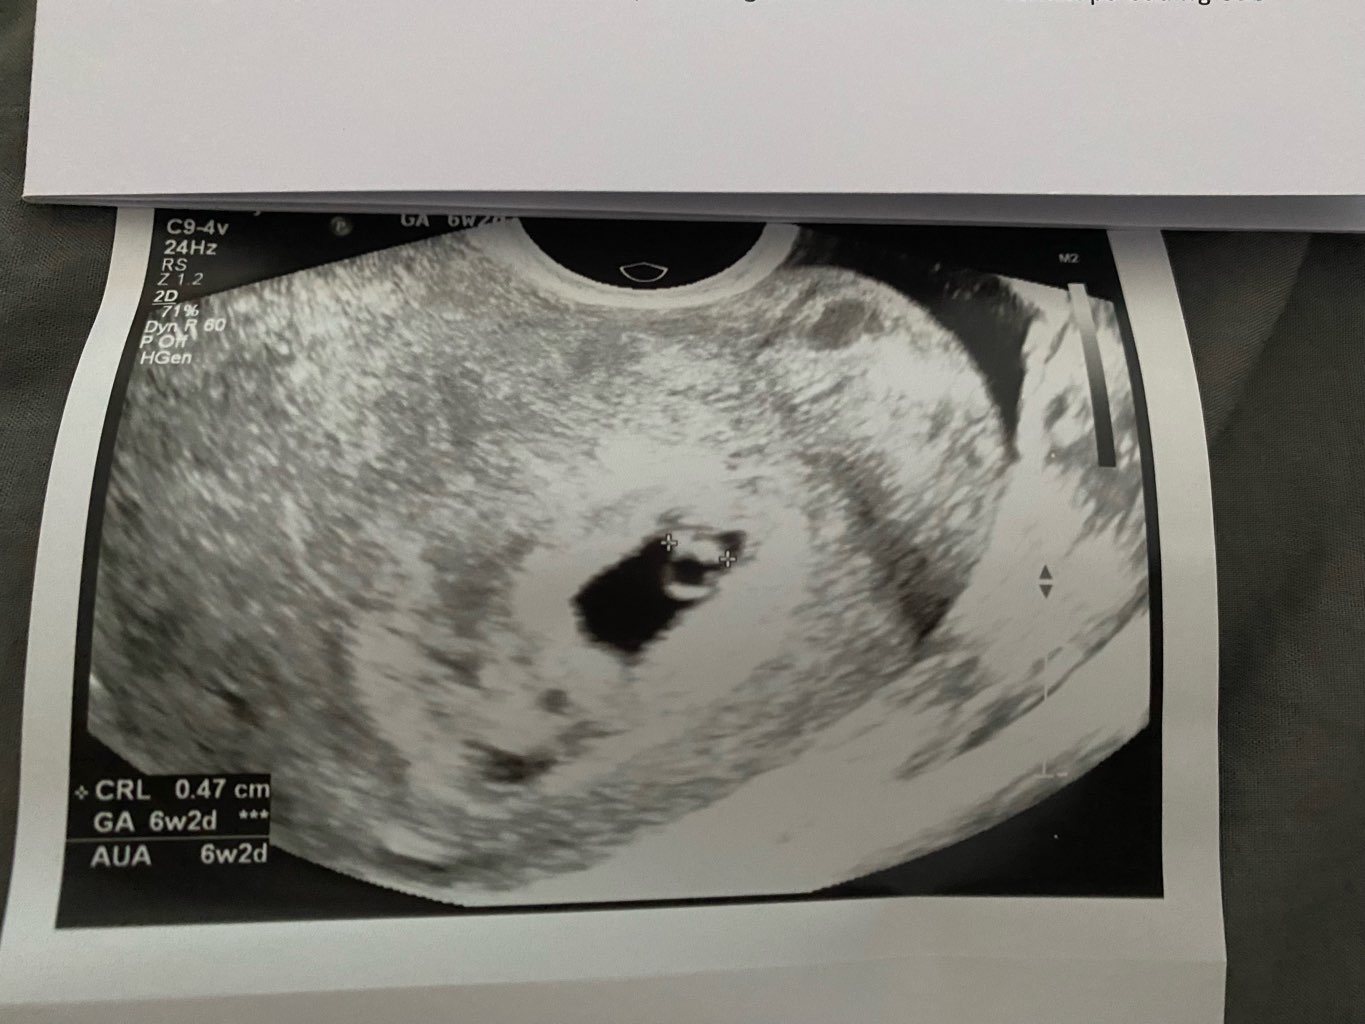

Kochane dzisiaj miałam wizytę tj wg OM 7+6 A wg USG 7+4

miałam ta przyjemność usłyszeć serduszko ,dzidzia ma 1,30cm i już kocham je ponad wszystko